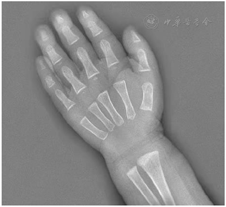

肝功能提示转氨酶升高,血常规提示中性粒细胞和血红蛋白降低。左手腕部正位X线片显示骨龄明显落后于1岁。肠镜检查发现结直肠黏膜糜烂,肠腔内可见较多油性食物残渣附着。全外显子测序显示患儿SBDS基因复合杂合突变,c.258+2T>C来自父亲,为已知致病突变,c.100A>G来自母亲,尚未报道。

血常规:白细胞4.88×109/L,血红蛋白103 g/L,血小板219×109/L,中性粒细胞计数0.52×109/L;肝功能:谷丙转氨酶256.8 U/L,谷草转氨酶151.6 U/L。铁蛋白升高(848.7 ng/ml),血气分析、肾功能、心肌酶、电解质、血糖、三酰甘油、脂肪酶、凝血功能、体液及细胞免疫功能、铜蓝蛋白、粪常规、腹部彩超均正常,甲状腺功能:甲状腺素62.93 nmol/L,偏低,余正常。骨髓象:有核细胞减少,中性粒细胞减少,红系比例减低,血小板散在聚集可见,淋巴细胞比值增高。粪培养提示菌群失调;自身抗体谱、血尿遗传代谢筛查、巨细胞及EB病毒IgM抗体及DNA、T-SPOT、粪便艰难梭菌毒素检测、叶酸、维生素B12均阴性。左手腕部正位X线片显示骨龄明显落后于1岁(图1)。胃镜示上消化道胃镜检查未见异常;肠镜示结直肠黏膜糜烂样改变,肠腔内可见较多油性食物残渣附着(图2)。胃肠镜病理示:十二指肠黏膜绒毛低平,固有层水肿,淋巴管轻度扩张,散在淋巴细胞、浆细胞浸润。回肠末端黏膜绒毛低平,固有层脉管轻度扩张,淋巴组织增生。大肠黏膜组织慢性炎症,固有层内嗜酸性粒细胞增多,26个/HP(图3)。

SDS已报道的病例临床表现复杂多样,典型的临床症状包括胰腺外分泌功能障碍相关的吸收不良、脂肪泻和生长迟缓,单一或多种血细胞减少血液异常并骨髓增生异常综合征和急性粒细胞白血病,以及身材矮小、骨畸形、神经异常、肝功能不全、重症感染等。一项来自意大利的研究显示,粒细胞缺乏、胰腺外分泌功能不全、骨骼异常发生率分别为80%、75%和50%[14]。随着时间的推移,患者之间,甚至同一个人前后的临床表现差异很大[15]。吸收不良、脂肪泻、脂溶性维生素缺乏和生长障碍是胰腺外分泌障碍的典型临床表现,多于婴儿期起病,随年龄增长,生长迟缓更为明显。本例患儿婴儿期起病,反复腹泻,生长发育迟缓、营养不良,与胰腺外分泌功能障碍的临床表现相符。SDS患者骨骼发育异常主要表现为身材矮小,干骺端发育不良,骨龄落后,骨质疏松,全身性骨质减少,肢体畸形等[16,17]。该患儿明显身材矮小、骨龄明显落后,符合骨骼发育异常的主要表现。此外,心脏、胃肠道、肾脏等先天性畸形表现均有报道。